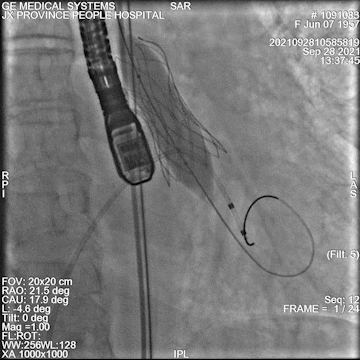

后扩

最终造影

术中情况:术中超声及造影评估,左冠灌注未受影响,瓣膜释放后无明显下滑,洪浪院长术中使用VitaFlow Liberty™进行操作,并精准释放,超声及时辅助评估,VitaFlow二代可回收功能给术者增加信心,可以更放心、大胆的挑战高风险病例。